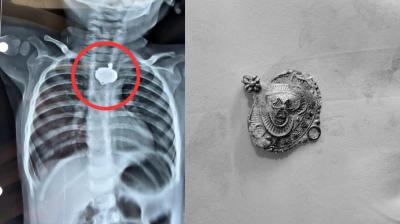

बड़वानी में 9 माह के बच्चे की आहार नली में फंसा मंगलसूत्र, डेढ़ महीने बाद एक्स-रे से खुलासा

24 Nov, 2025 08:30 AM IST | INTERNALNEWS.IN

बड़वानी: रविवार को जिला अस्पताल में एक बेहद संवेदनशील और हैरान करने वाला मामला सामने आया. जब 9 माह के एक बच्चे के गले में मंगलसूत्र फंसा हुआ देखा गया. घटना...